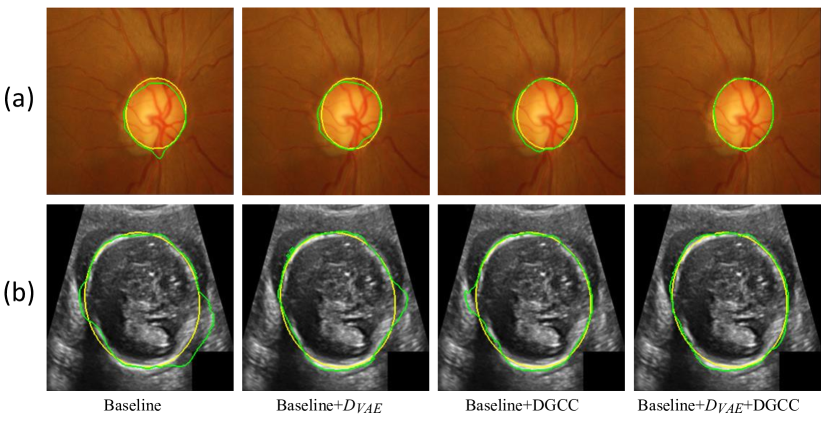

We first evaluate the effectiveness of our pseudo label generation method. For an ablation study of our , we started with the baseline of training a CycleGAN [30] without and DGCC. Table 2 shows quantitative evaluation results of the output of on the validation set with different latent vector length of the VAE. It can be observed that the best performance is achieved when the length of latent vector is 32. Fig 5 shows that the optimal value of hyper-parameter is 1.0, and the performance of does not change much when is around 1.0. We also compared our with three counterparts: 1) the baseline not using , 2) our without , 3) replacing the VAE with beta-VAE [62] where the latent vector length was 32, denoted as (beta). Quantitative evaluation based on the testing set in Table 1 shows that our outperformed the counterparts, and compared with not using , it improved the average Dice from 0.909 to 0.918 for optic disc segmentation and from 0.904 to 0.918 for fetal head segmentation, respectively. Fig. 3 demonstrates the effectiveness of our VAE-based discriminator on the output of .

We further evaluated the effectiveness of our multi-scale DGCC module by ablation studies. We compared it with two variants: 1) DGCC(l) that only calibrates the low-resolution feature map obtained by the bottleneck of ; 2) DGCC(h) that only calibrates the high-resolution feature map before the last convolution block of . The quantitative evaluation results of these variants combined with our baseline model are shown in Table 3. It can be observed that our multi-scale DGCC has a higher performance than DGCC(l) and DGCC(h), which demonstrates that multi-scale calibration performed better than single-scale calibration of the pseudo label generator . We also compared the calibrated result at of our DGCC with the result at (i.e., before calibration) of our DGCC module, which is denoted as DGCC(). The quantitative results in Table 3 and qualitative results in Fig. 4 show that the calibration helps to reduce and even remove some noise in the output of . In addition, Fig. 3 and Table 3 show that combining our with DGCC outperforms the other variants.